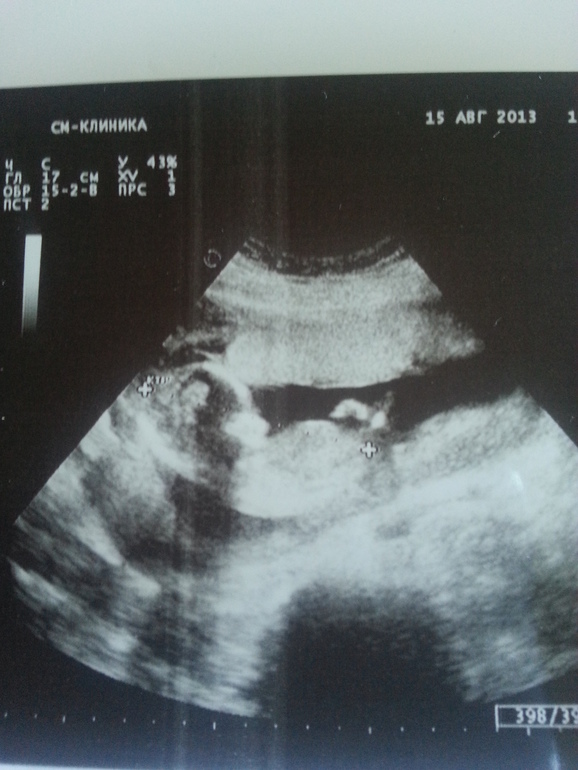

На прошлой неделе сильно заболел живот, сразу побежала к врачу, выписали дюфастон и прокапать магнезию. Теперь все хорошо, но опасаясь за малыша решила сделать очередное узи.С нами все хорошо, с 25-го числа сказали идти на второй скриниг, тогда возможно скажут и пол

Какая фотка:) а мы только 30 пойдем на второй скрининг :) жду не дождусь встречи с малышкой:) надеюсь пол точно смогут сказать:) в 13 нед. предположили девочку :)

ой ничего себе, какой уже крупнячок)) с 25 числа, это сколько будет уже срок?